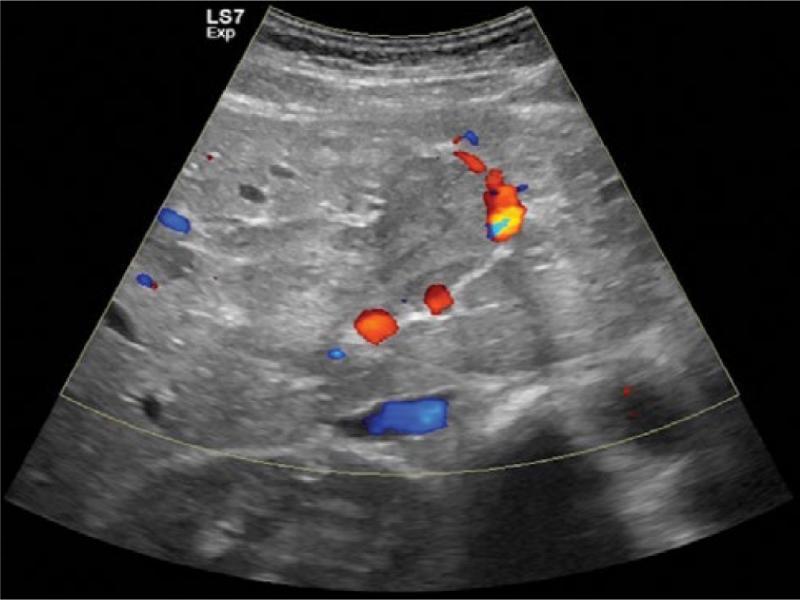

Fig. 2.

Color Doppler US image reveals the presence of diagnostic arterial flow within the tumor thrombus